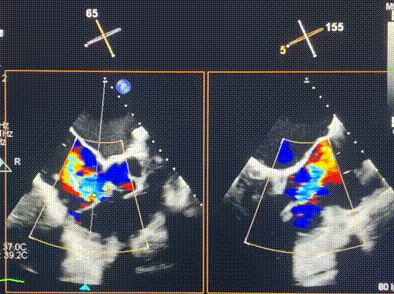

術前超聲提示重度三尖瓣反流

接受本次LuX-Valve Plus治療的是一位三尖瓣重度反流的高齡女性,患者早前曾由于二尖瓣疾病行經(jīng)導管二尖瓣置換術,植入Tendyne瓣膜一枚,且有ICD植入史。術前CT分析結果顯示,瓣環(huán)大小為47.6mm,血管無明顯迂曲和鈣化。由于患者三尖瓣解剖結構復雜,二尖瓣位人工瓣膜造成的超聲偽影和ICD導線的干擾使得歐洲沒有其他合適的商業(yè)化和臨床試驗的產(chǎn)品可以對其進行治療。經(jīng)過Rodrigo Estévez-Loureiro教授團隊的詳盡術前評估,認為LuX-Valve Plus經(jīng)導管三尖瓣置換系統(tǒng)可以對該患者進行有效的治療。因此,Rodrigo Estévez-Loureiro教授團隊最終決定使用這一中國創(chuàng)新器械為患者進行手術。法國波爾多里爾大學附屬醫(yī)院的Thomas Modine教授與加拿大圣保羅醫(yī)院的Anson Cheung教授全程線下指導本次手術。